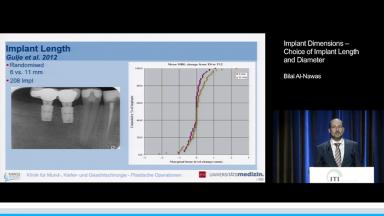

When severely atrophic jaws are encountered, many different implant-prosthetic approaches have been used to address this condition. The more-aggressive protocols call for bone grafting followed by placement of standard-diameter endosseous implants. This presentation focuses on clinical applications of implants with reduced dimensions. In the setting of reduced alveolar bone height, short dental implants offer clinicians a pragmatic option to facilitate prosthetic restoration when confronted with anatomic limitations. When short implants are employed, implant design and surface properties become very important. Likewise, diameter-reduced implants must be used judiciously to avoid complications.

- recognize the advantages and limitations of short and diameter-reduced implants

- define the implant length and diameter that qualify as a ‘short implant’ and ‘diameter-reduced implant’ respectively

- explain how overload affects implant survival